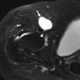

Fluid in iliopsoas bursa